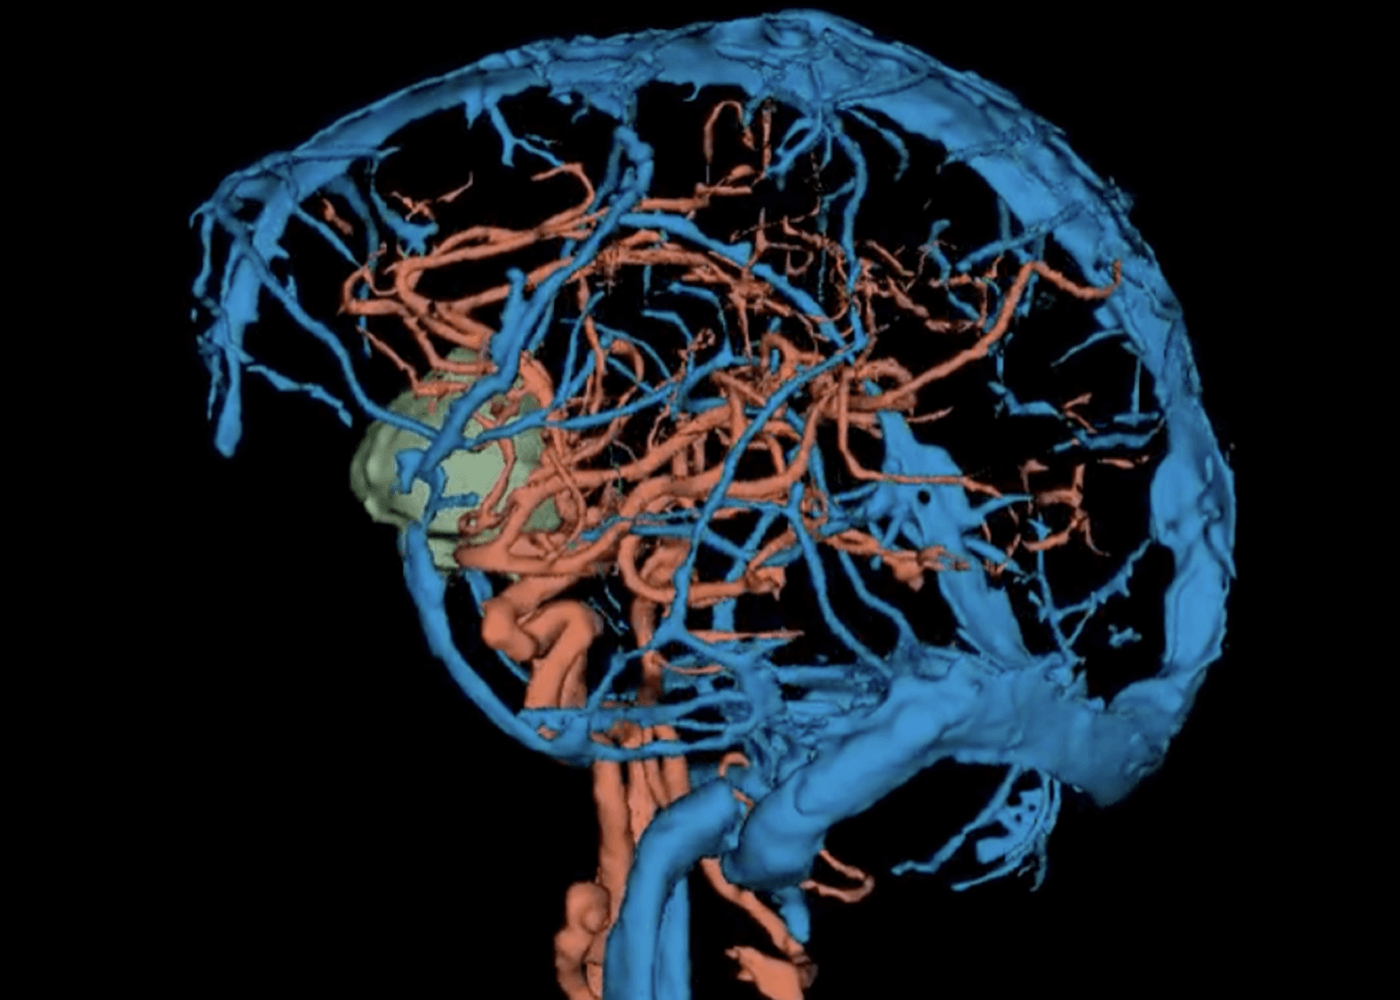

Vessel and Brain tumor segmentation

Brain Tumor: radiology labeling on 3D Slicer